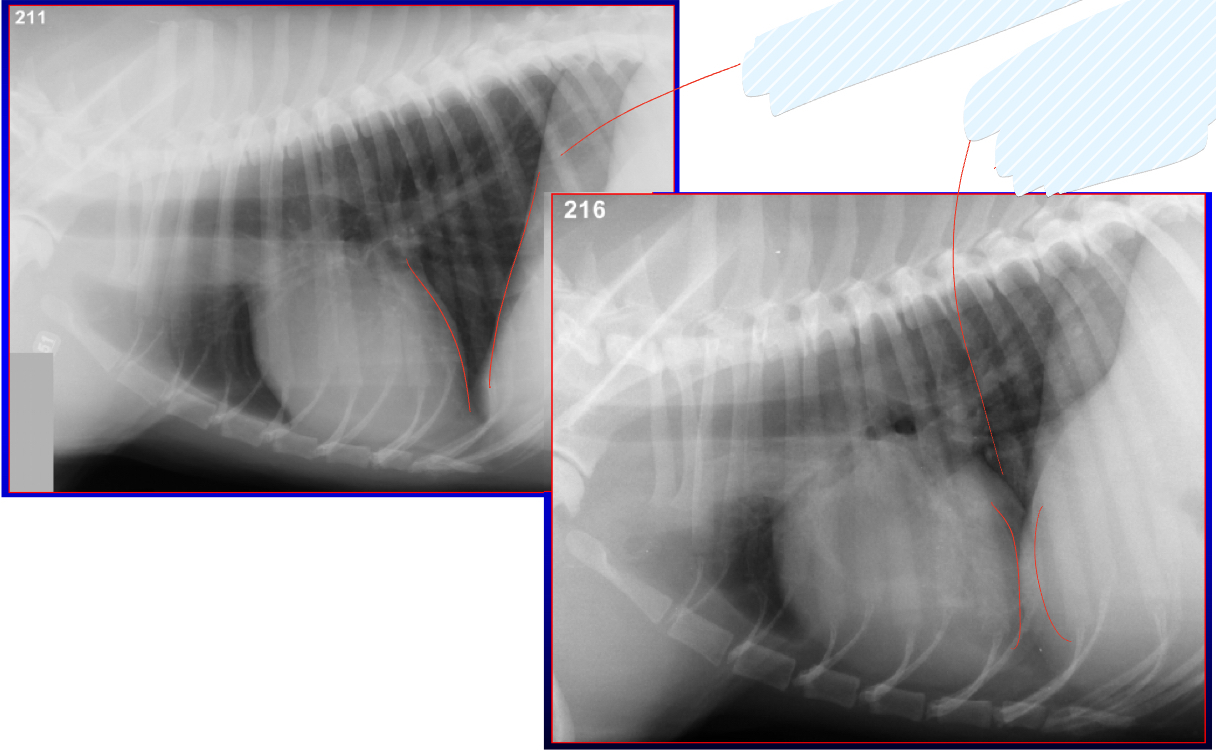

which of the following is a more appropriate radiograph

Upper left- inspiration- more space between heart and diaphragm

Lower right: exhalation- not as much space